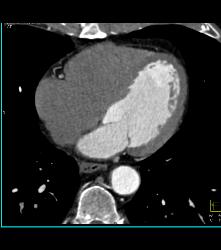

Lymphoma With Abdominal Disease